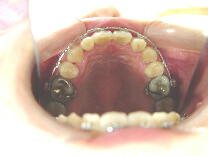

症例3 (30代 女性) 右下顎切歯先天性欠如

左右上顎第一小臼歯・右下顎第一小臼歯抜歯例

初診から2年9ヶ月後